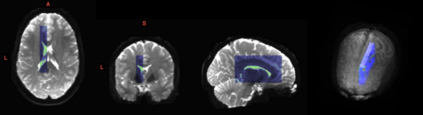

We present an information-theoretic approach to the registration of images with directional information, and especially for diffusion-Weighted Images (DWI), with explicit optimization over the directional scale. We call it Locally Orderless Registration with Directions (LORD). We focus on normalized mutual information as a robust information-theoretic similarity measure for DWI. The framework is an extension of the LOR-DWI density-based hierarchical scale-space model that varies and optimizes the integration, spatial, directional, and intensity scales. As affine transformations are insufficient for inter-subject registration, we extend the model to non-rigid deformations. We illustrate that the proposed model deforms orientation distribution functions (ODFs) correctly and is capable of handling the classic complex challenges in DWI-registrations, such as the registration of fiber-crossings along with kissing, fanning, and interleaving fibers. Our experimental results clearly illustrate a novel promising regularizing effect, that comes from the nonlinear orientation-based cost function. We show the properties of the different image scales and, we show that including orientational information in our model makes the model better at retrieving deformations in contrast to standard scalar-based registration.